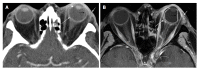

Orbital inflammatory disease (OID) represents a collection of inflammatory conditions affecting the orbit. OID is a diagnosis of exclusion, with the differential diagnosis including infection, systemic inflammatory conditions, and neoplasms, among other conditions. Inflammatory conditions in OID include dacryoadenitis, myositis, cellulitis, optic perineuritis, periscleritis, orbital apicitis, and a focal mass. Sclerosing orbital inflammation is a rare condition with a chronic, indolent course involving dense fibrosis and lymphocytic infiltrate. Previously thought to be along the spectrum of OID, it is now considered a distinct pathologic entity. Imaging plays an important role in elucidating any underlying etiology behind orbital inflammation and is critical for ruling out other conditions prior to a definitive diagnosis of OID. In this review, we will explore the common sites of involvement by OID and discuss differential diagnosis by site and key imaging findings for each condition.